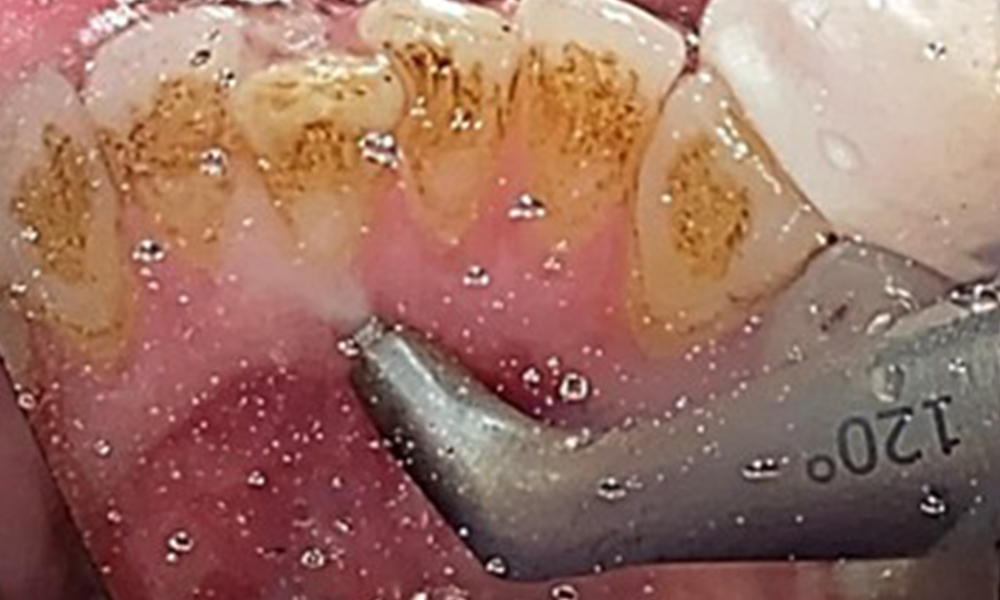

Nahaufnahme der Zähne

Abb. 5: Nahaufnahme der Zähne 45-47. Grüne Pfeile zeigen Attritionen und Erosionen im Bereich der bukkalen Höcker mit partiellem Schmelzverlust, © Dr. R. Krapf

Dental zeigt sich ein vollbezahntes Gebiss mit 28 Zähnen. Auffällig sind Erosionen und Attritionen

(Abb. 4, Abb. 5). Der Patient trägt seit vielen Jahren nachts eine Schiene mit adjustiertem Aufbiss aufgrund Bruxismus. Die Erosionen sind auf den langjährigen Konsum isotonischer Getränke zurückzuführen. Parodontaler Knochenverlust und aktive kariöse Läsionen sind nicht vorhanden.